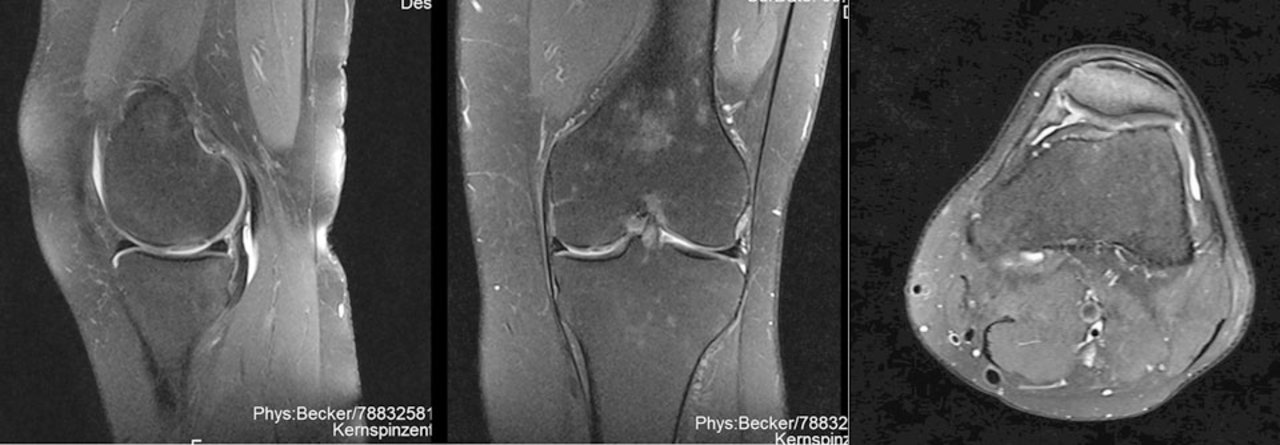

Solche Knorpelschäden wie bei einer 64-Jährigen (links) oder einem 26-Jährigen durch Kollision des Knies mit einem Surfbrett (rechts) lassen sich auch mit einem kleineren Eingriff beheben. Solche Knorpelschäden wie bei einer 64-Jährigen (links) oder einem 26-Jährigen durch Kollision des Knies mit einem Surfbrett (rechts) lassen sich auch mit einem kleineren Eingriff beheben. © Schneider S et al. Hamburger Ärzteblatt 2021; 75: 30-31 © Hamburger Ärzteverlag, Hamburg

Das Verfahren eignet sich laut Dr. Schneider sowohl bei jungen aktiven Sportlern mit Verletzungen als auch für ältere Menschen mit degenerativen Knorpelschäden. Er berichtet über einen 26-Jährigen, der nach Kollision mit einem Surfbrett über Knieschmerzen klagte. Ursache war ein Knorpeldefekt im Bereich der Patella, der erfolgreich mittels Minced-Cartilage-Technik versorgt wurde. Nach zehn Monaten konnte der Mann alle sportlichen Aktivitäten, einschließlich Joggen und Surfen, in vollem Umfang wieder aufnehmen.

Auch eine 64-jährigen Patientin mit einem viertgradigen Knorpelschaden im Bereich der Femurkondylen profitierte von dem Verfahren: Sieben Monate nach dem Eingriff war der Defekt vollständig gefüllt und die ältere Dame konnte ohne Schmerzen wieder Sport treiben.